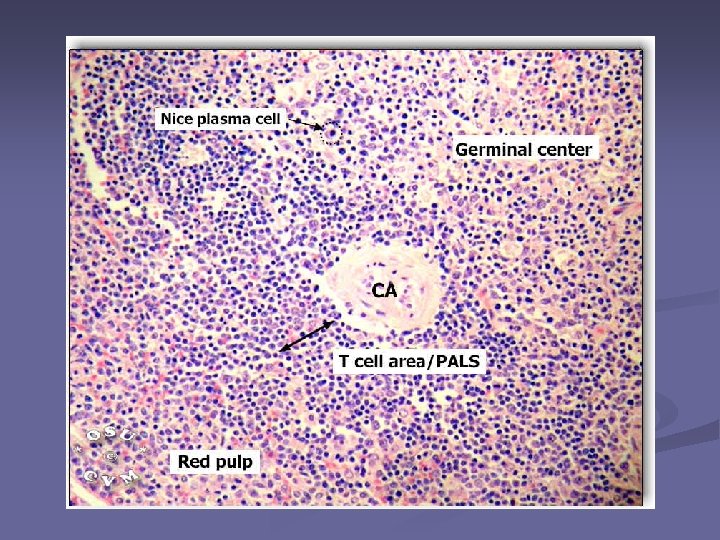

n Pulpa alba Parenchimul - formata din tesut limfoid dens - se organizează in jurul arterelor Rol: procesele imune Pulpa rosie – tesut reticular lax, lacunar, – se organizeaza in jurul sinusurilor venoase. Rol: filtrează sângele Pulpa alba n Pulpa rosie

Structura pulpei albe formata din tesut limfoid dens - se organizează in jurul arterelor Rol: procesele imune n n arteră centrală ţesut limfoid = teaca limfoidă periarterială (PALS)- ly T (in special CD 4, n putine CD 8) n Periferie - Ly B

n La contactul cu atg, ly B se transformă blastic → folicul secundar cu centrul germinativ – pol clar : limfoblaste– spre PR - pol întunecat : plasmocite, ly B memorie – spre a centrală Arteriola va ocupa o poziţie excentrică Structura alcătuită din artera excentrica+ teaca limfoida + foliculul secundar = corpuscul splenic Malpighi (folicul splenic) În PA Limfocitele T in tecile periarteriale(PALS); Limfocitele B - in nodulii limfoizi – in zona marginală (între PA şi PR)

Corpuscul splenic Malpighi (folicul splenic)

Parenchimul splinei